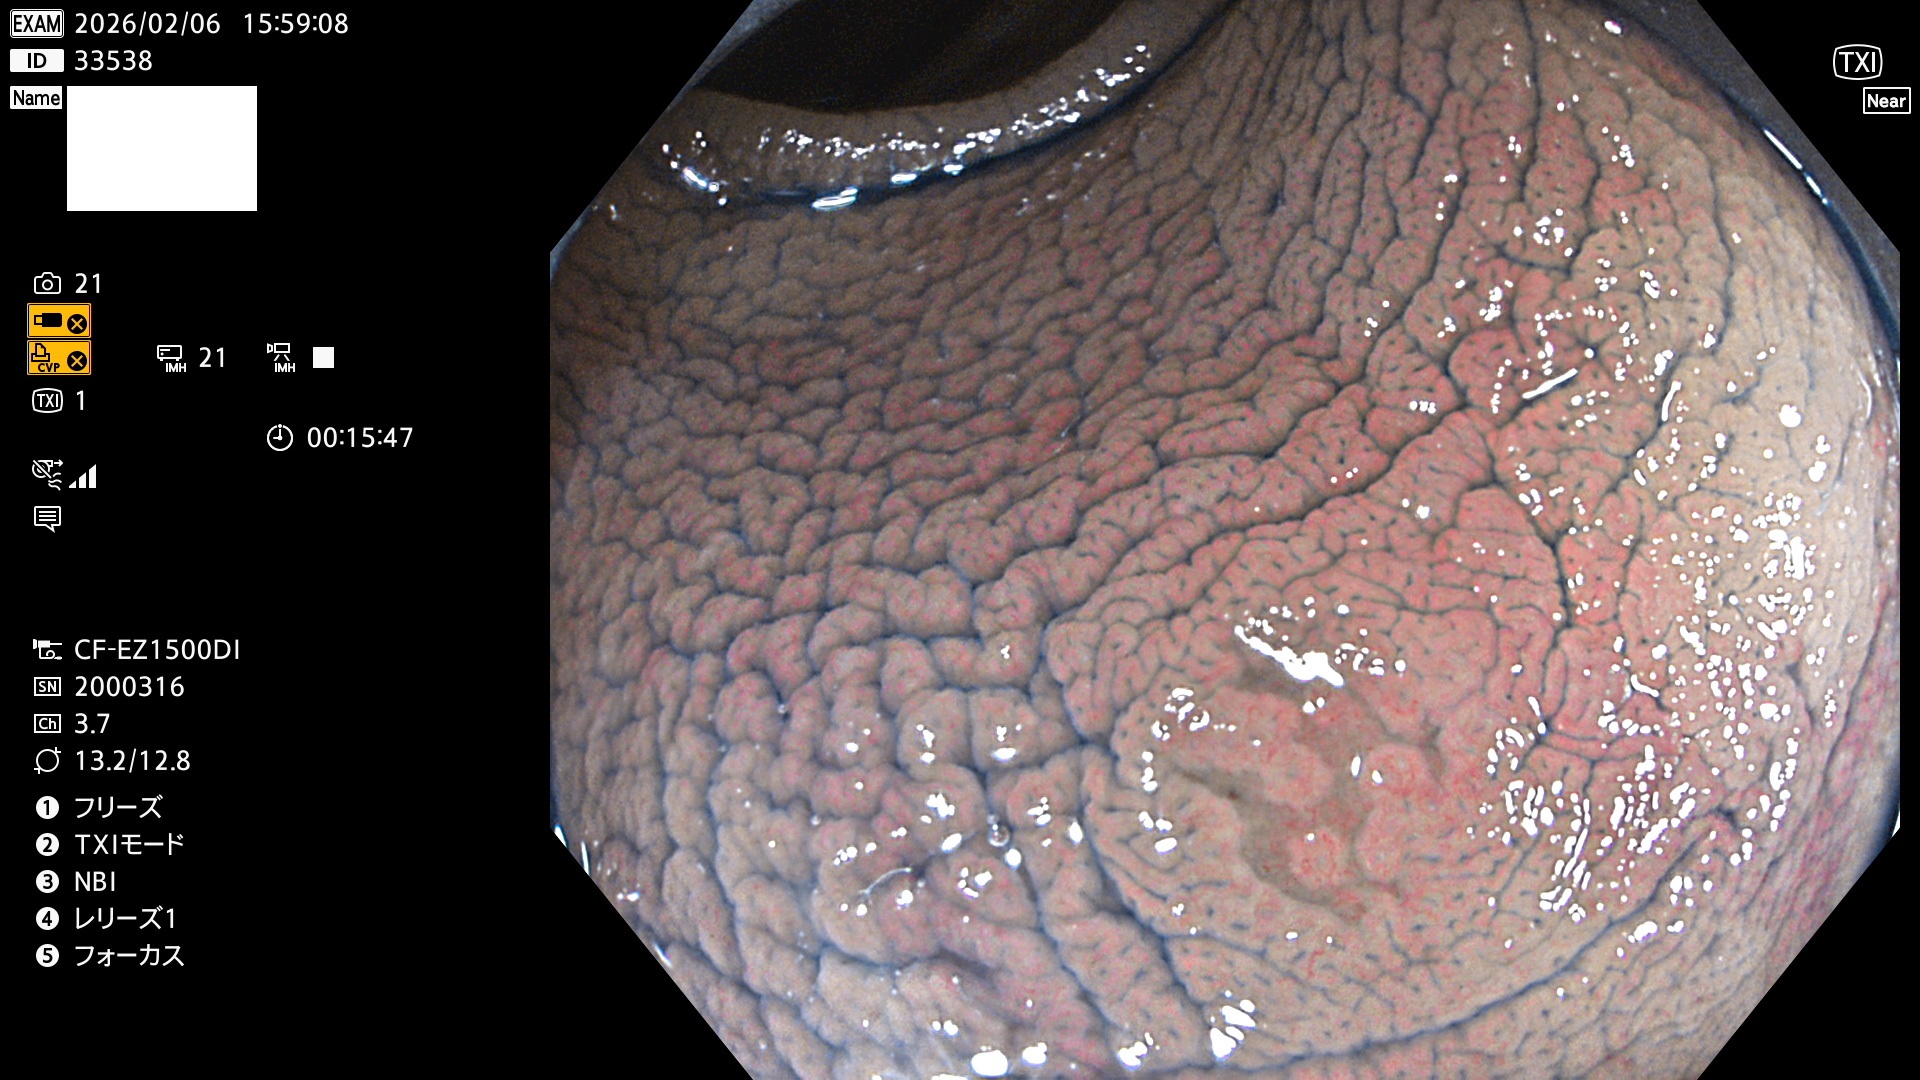

完全に平坦な物をUb、陥凹している物をUcと呼びます。Ubは認識が困難で、Ucはびらん(炎症)と紛らわしいために見落とされやすく、「内視鏡後・大腸癌」の原因になります。

専門的)Uc=De Novo癌? 内視鏡の解像度が低かった時代、このような説もありました。しかし今日の高精度内視鏡では良性の微小なUc型腺腫(APC遺伝子異常の腺腫)が日常的に見つかります。Ucこそが多段階発癌(Adenoma-Carcinoma Sequence)のMain Routeです。

毎週の検査(木・金・土・日)に発見されたUbとUc型・腺腫を、その週の日曜の夜にUPし1週間、提示します。

2026年2月5日〜2月8日の4日間(40件)9個 (Uc_ADR=9個/40人=23%)